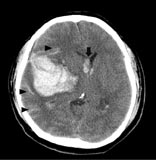

現行的做法是,如果病人描述的頭痛符合雷擊式頭痛的特徵,醫師就會安排檢查去排除是不是有動脈瘤。值得注意的是,有些病患在動脈瘤真的要破裂前的幾天到幾週,有比較輕微的頭痛,就像預告即將到來的災難,被稱為警告頭痛(warning Headache)或是哨兵式頭痛(Sentinel Headache)。筆者在多年前遇到一個病人,因為近來幾天屢屢發作輕微頭痛,醫師安排了電腦斷層並轉來我的門診。預定返診當天早上,病人覺得已經不再頭痛不想來,但太太覺得不妥而代替他來看報告。我在斷層中發現一個動脈瘤(如:圖A),大驚之餘要求馬上帶病人來急診,不料等太太回到家,動脈瘤竟已破裂出血(如:圖B),病人癱瘓在地。經送來急診及後續開刀,雖有改善,仍殘留肢體無力等症狀。後經病人同意,我把這個案例發表在《台灣神經學雜誌》上。

圖B:圖中白色一團即為腦出血,黑色箭頭代表蜘蛛下腔出血,黑色箭號則是代表腦室出血。